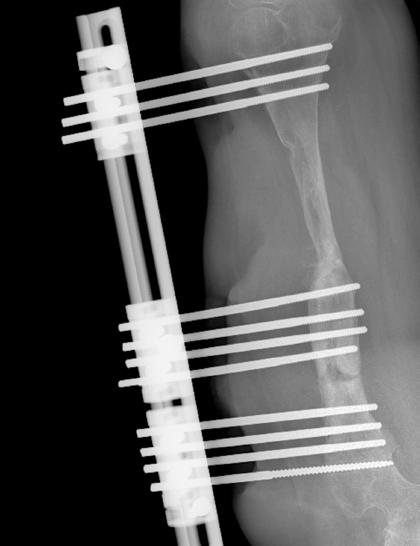

Two refurbished C-arms and accompanying X-ray equipment will allow medical professionals to understand conditions more closely and precisely treat patients suffering from broken or malformed bones. New surgical tables and tools will enable the operating theater to reach new heights in quantity and quality of care.

Executive Director Elly Chemey says, “We are continuously grateful to The Beit Trust for donating medical equipment to us. This donation included a critically needed C-arm that enabled our surgeons to monitor the progress of the highly specialized surgeries they perform and make decisions accordingly. The C-arm they donated has fluoroscopy technology that enables the machine to provide realtime, high-resolution X-ray images.”